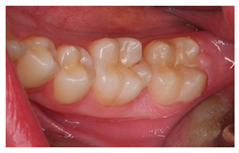

| 1 | A 21-year-old healthy patient visits the dental clinic for a check-up. The patient does not present any symptoms nor other oral clinical signs, except visible plaque in all quadrants, which extends towards the gingival third of various teeth. | ![]() | Regarding the distal pit of tooth 3.6 What is your clinical diagnosis? Which complementary diagnostic tests would you perform to confirm your diagnosis for tooth 3.6? Order the answers from more to less relevant for the diagnosis of this case. |

| [13,14] [30,31] | |

| Which treatment alternative would you select for this case? Order the answers from more to less relevant for the treatment of this case. |

| |||||